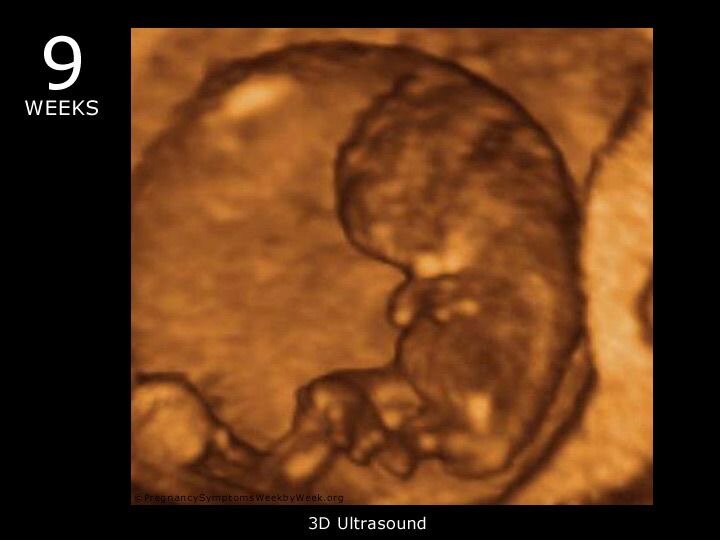

8-9 недель беременности и самая частая ошибка врача УЗИ

Итак, наш малыш уже стал побольше, Он ростом уже 20 -30 мм и весом до 5-6грамм.

На этих неделях также происходит активное развитие органов и систем плода , продолжает развиваться головной мозг ( он уже разделён на два полушария, которые можно увидеть на УЗИ), развился мозжечок, внутренние органы , дыхательная система , скелетная системы ( появляются точки окостенения и вырисовываются структуры длинных трубчатых костей конечностей и позвоночника). На Узи этим точкам окостенения соответствуют участки ярко белого цвета, которые говорят о плотности структуры, тк ультразвуковые лучи не проходят через костные структуры. Ближе к 9 неделе, пальцы на ногах и руках начинают дифференцироваться

Ближе к 9 неделе, пальцы на ногах и руках начинают дифференцироваться раздельно, плод уже больше становиться похож на человека, а не на амфибию.

На голове сформировались уши, есть зачатки ноздрей, носа, рта, сформировалось верхнее веко и малыш может открывать и закрывать глаза.

НА УЗИ можно увидеть движение ручками и ножками, а также сам малыш, как рыбка в воде, может совершать различные движения.

Сердечко малыша активно бьется и можно на Узи зафиксировать частоту, в среднем 120-160 уж в минуту, но помним, что в ранних сроках для плодов характерно сердцебиение ближе к 160 и чуть выше- это нормально! По Узи увидеть четыре камеры сердца пока ещё невозможно.